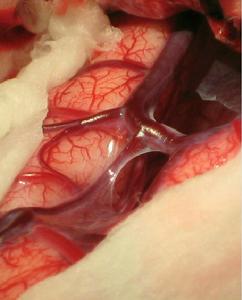

3、手術切除 血管內栓塞失敗或無栓塞指征者,手術切除不失為有效的治療手段。手術適應證為:(1)合併顱內血腫,有占位效應;(2)引流靜脈呈靜脈瘤樣擴張,有破裂可能。開顱翻骨瓣時要特別小心,因為硬腦膜上充滿了動脈化的靜脈血管。如瘺口位於竇壁,血管內栓塞欠佳者,可開顱切開竇壁,直接行竇內銅絲填塞,效果肯定。